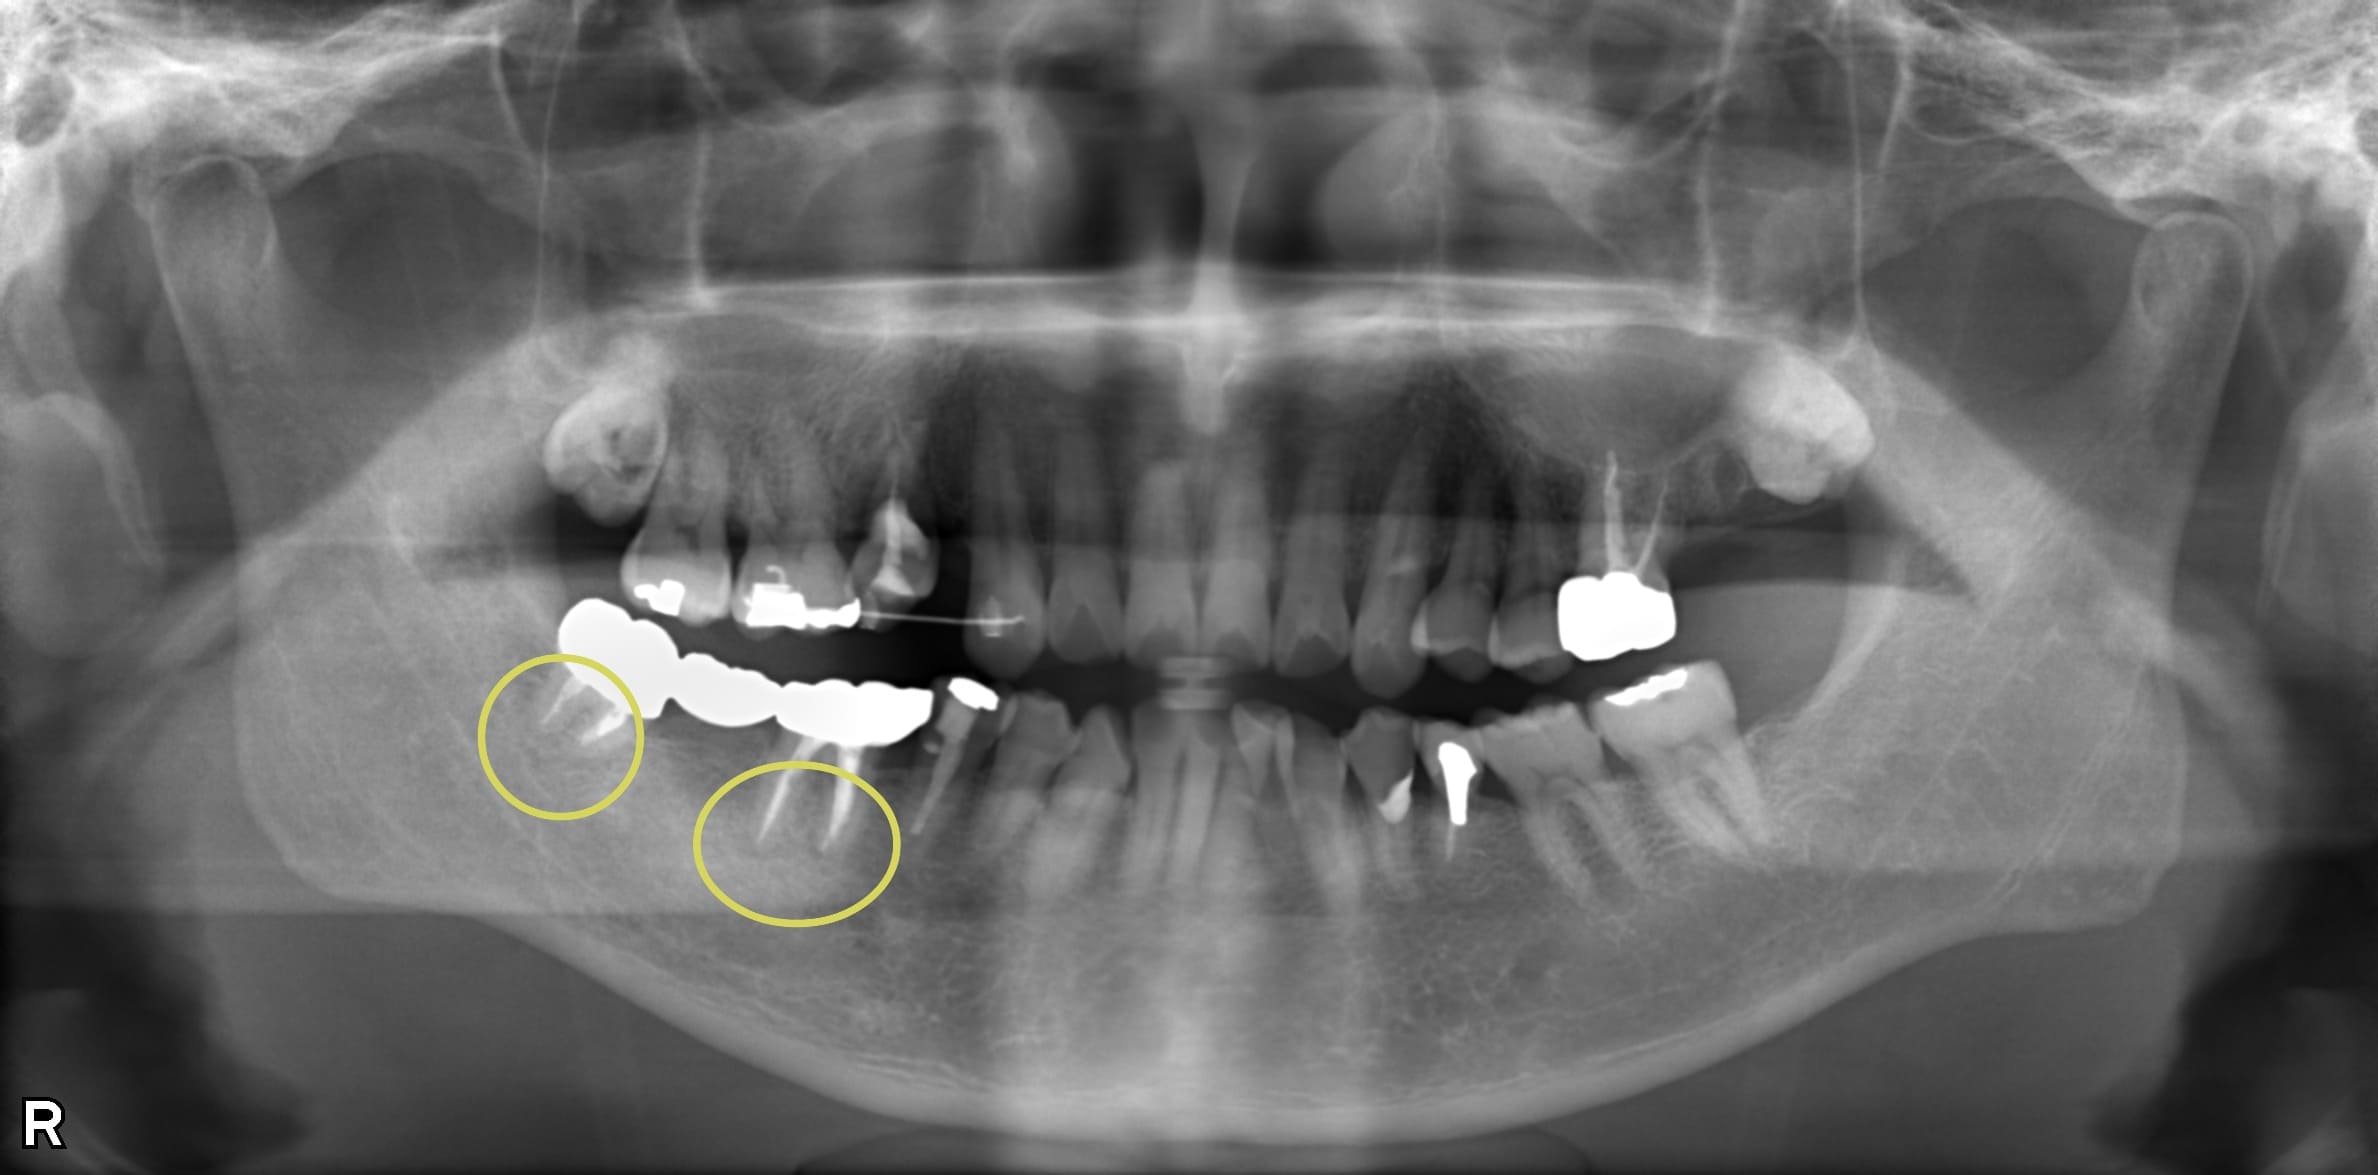

症例紹介